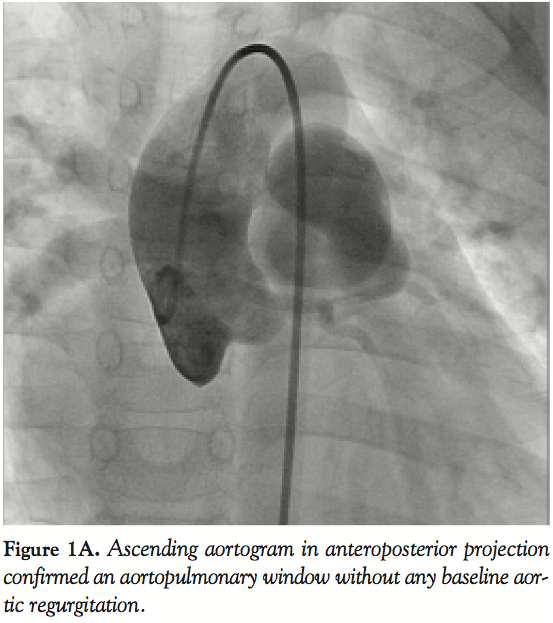

Catheterization revealed pulmonary artery pressure of 54/36 mmHg (mean of 42 mmHg), aortic pressure of 104/58 mmHg and Qp:Qs of 2:1. An ascending aortogram in anteroposterior projection confirmed the diagnosis (Figure 1A). The defect was crossed from the aorta with a Judkins right coronary catheter and an angled-tip, 0.035-inch glide wire, which was exchanged for a 300 cm long noodle wire (AGA Medical, Plymouth, Minnesota). Crossing of APW from pulmonary end was not attempted. A stable arteriovenous wire loop was established by snaring the noodle wire from the pulmonary artery with a 15 mm gooseneck snare (Microvena Corp., White Bear Lake, Minnesota) introduced from the femoral vein. A 6 Fr Amplatzer duct-occluder delivery sheath (AGA Medical) was introduced over the wire and placed across the defect into the ascending aorta. A 10/8 mm Amplatzer duct occluder with its attached delivery cable was then inserted through the delivery sheath, and its retention disk was deployed into the ascending aorta. The entire assembly was pulled back until the aortic disk blocked the APW from the aortic side.

After confirming precise position of the device on transthoracic echocardiography and control angiography, the rest of the device was deployed on the pulmonary arterial side, by withdrawing the delivery sheath. Post-release angiogram revealed no residual shunt. However, there was new grade I mild AR (Figure 1B) that was also confirmed on color doppler echocardiography (Figure 2). Clinically no murmur was audible and aortic pulse pressure had decreased as well as pulmonary artery pressure (Aortic pressure 112/72 mmHg; pulmonary artery pressure 40/25 mmHg; mean 33 mmHg). As the defect was remote from aortic valve and there was no impingement on it, the result was accepted. On follow-up at 3 months and 6 months, patient was asymptomatic. Importantly, there was a progressive decrease in the grade of AR from mild to only trivial grade at 6 months (Figure 3).